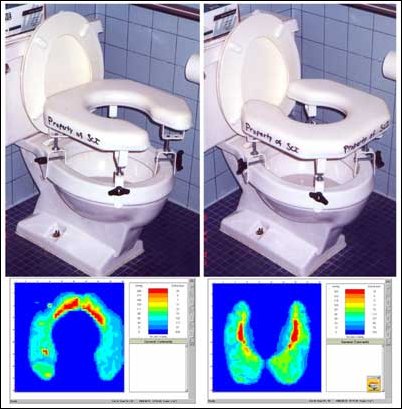

Podkładkę z czujnikami umieszcza się pomiędzy siedziskiem a pośladkami osoby siedzącej, informacje o wywieranym ucisku na skórę są wyświetlane na monitorze. Kolory i numery na monitorze odpowiadają poziomowi ucisku wywieranego na skórę pacjenta wyrażane w milimetrach słupka rtęci (mmHg). Każdy z czujników pokazuje swój odczyt ciśnienia, a więc odczyt całości to obraz 1296 oddzielnych wyników. (Patrz zdjęcie 2.)

Rysunek 2: Mapa Ucisku pokazuje obszary o małym i dużym ucisku podczas siedzenia. Kolory i numery na ekranie odzwierciedlają poziom ucisku wyrażany w milimetrach słupka rtęci. (mmHg).

Zdjęcie 2 pokazuje dwie Mapy Ucisku tej samej osoby siedzącej na dwóch różnych poduszkach. Poduszka z prawej strony ukazuje nam korzystniejszą Mapę Ucisku dla pacjenta i prawdopodobnie byłaby lepszym wyborem do codziennego stosowania.

Mapy Ucisku pokazują różnorodność wśród osób używających ten sam sprzęt. Zdjęcie 3 pokazuje dwie różne osoby na tej samej poduszce. Niższy i tęższy pacjent (z lewej) wykazuje lepsze rozłożenie ucisku na skórę, natomiast u wyższego i szczuplejszego pacjenta (z prawej) siedzącego na tej samej poduszce mapa ucisku pokazuje zupełnie inne wartości wskazujące na wyższe ryzyko powstania odleżyn. Można z tego wnioskować, że nie należy generalizować odczytów Mapy Ucisku przeprowadzonych na tej samej poduszce dla różnych osób – twierdzi doktor Betz.

Zdjęcie 3: Dwie różne osoby siedzące na tej samej poduszce na wózku mają zupełnie różne odczyty.